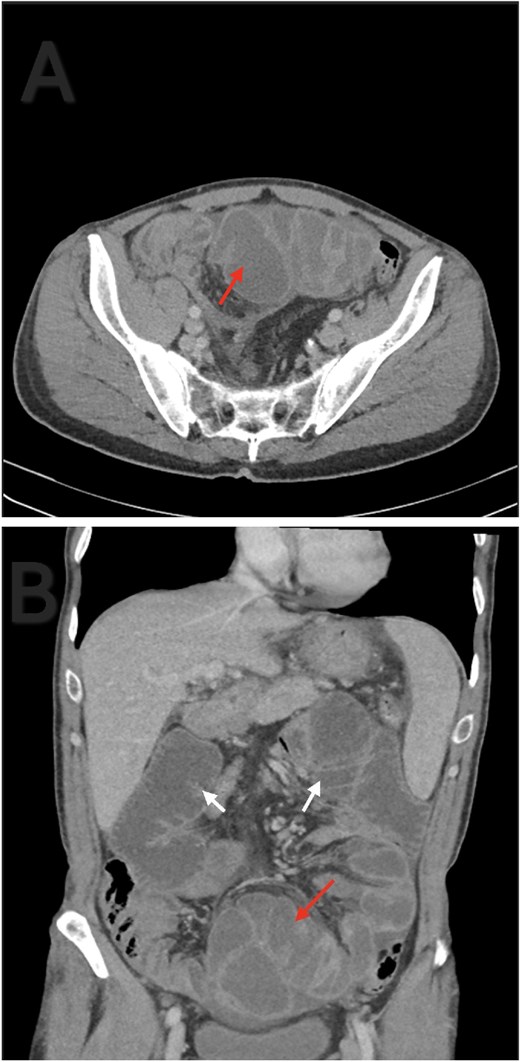

A 56-year-old male patient presented to the emergency department with generalized abdominal pain, obstipation, and vomiting for six days. On examination, there was diffuse generalized abdominal tenderness and a palpable mass in the hypogastric region. Contrast enhanced abdominal computed tomography (CT) revealed clustered ileal loops in the pelvis with multiple transitional zones and dilated proximal small bowel loops (Fig. 1).

Axial (A) and coronal (B) contrast enhanced abdominal CT. Ileal loops congregated at the pelvis (red arrow). Small bowel loops dilation (white arrow).